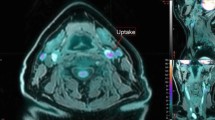

The Hybrid Viewer 2.0 software (Hermes Medical Solutions AB, Stockholm, Sweden) was used for image fusion and 18F-FDG uptake quantification. The CT angiography was used to guide drawing of the ROIs on the fused PET/CT slices. A plaque was defined as vessel wall thickening and a lumen contrast-filling defect on CT angiography (Figure 1).13 An experienced nuclear medicine physician (K.J.) drew ROIs around the entire vessel wall and lumen on all plaque-containing axial PET slices (Figure 2). ROIs were carefully placed to minimize the influence from 18F-FDG uptake in structures close to the plaque (e.g., lymph nodes, paravertebral muscles, or salivary glands). Blood pool activity was obtained from four ROIs placed in the lumen of the jugular vein away from structures with 18F-FDG uptake. Plaque localization in relation to the carotid bifurcation was recorded. The most cranial slice of the common carotid artery before the division was defined as the bifurcation. The pixel values in the PET images were converted into SUV normalized to lean body mass.5

For all plaque ROIs, SUVmax was obtained and the 18F-FDG uptake was quantified using the following approaches (Figure 2):